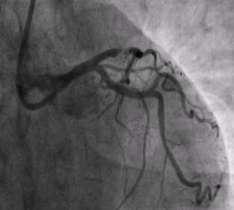

Sirolimus Eluting BioResorbable Vascular Scaffold System